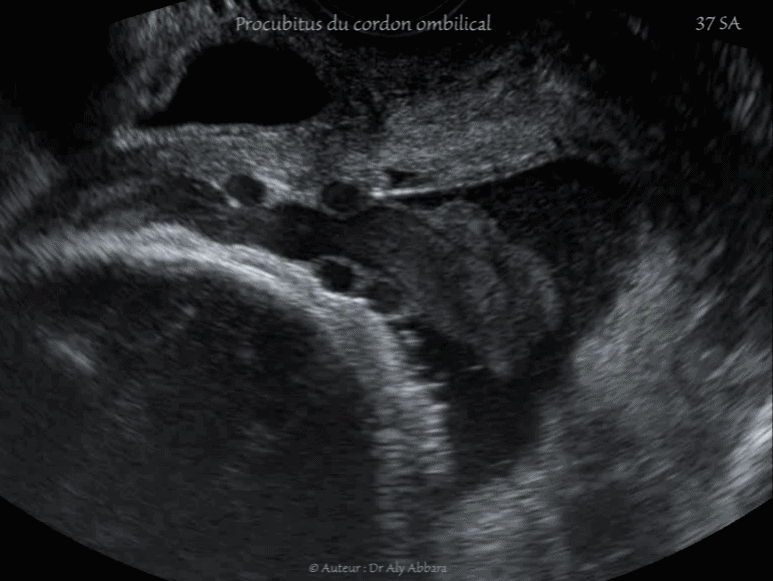

Procubitus du cordon ombilical - Grossesse de 37 SA

• Vidéos échographiques en mode 2D et en mode Doppler (Dynamic-Flow), à 37 SA, montrant un des aspects d'un procubitus du cordon (cordon ombilical praevia) : présence d'une anse du cordon ombilical au niveau du pôle inférieur de la cavité amniotique ; elle est coincée dans l'espace limité en haut, par le pôle céphalique foetal et en bas, par la partie basse du segment inférieur de l'utérus.

Cette anse funiculaire se trouve dans la poche des eaux formée par les membranes amniotique sur un col déjà très court (5 mm échographiquement) ; orifice interne inexistant, et au toucher vaginal, le col et très court, ouvert à 2 cm (l'aspect échographie d'un orifice externe fermé ne correspond pas à la réalité anatomique d'un col utérin largement ouvert).

Il s'agit d'un utérus contractile.

Le positionnement de cette anse funiculaire dans cet espace est appelé procubitus du cordon ; il s'accompagne d'un risque majeur de procidence du cordon ombilical au cours du travail, et surtout immédiatement après la rupture des membranes amniotiques.